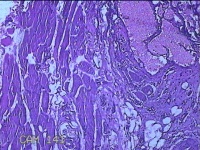

右手掌肿物

性别

女

年龄

32岁

临床诊断

1.右手掌肿物性质待查?右腕管综合征

一般病史

发现右手掌肿物疼痛伴拇示中指感觉迟钝约6年。

标本名称

大体所见

灰白粉红色肿物2.5x2x0.8cm一个,表面光滑,切开肿物呈实性,切面灰白粉红色,质软。